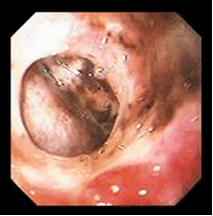

I – острая стадия. Язва в эту стадию при эндоскопическом осмотре представляет собой дефект слизистой оболочки различного размера, формы и глубины. Чаще всего она имеет округлую или овальную форму, края ее с четкими границами, гиперемированы, отечны. В ряде случаев край, обращенный к кардиальному отделу, несколько подрыт, а дистальный край более пологий, сглаженный (рис. 6, 7). Слизистая оболочка желудка или луковицы ДПК отечна, гиперемирована, складки ее утолщены и плохо расправляются воздухом, нередко имеются мелкоточечные эрозии, покрытые белым налетом и часто сливающиеся в обширные поля. Глубокие язвенные дефекты часто имеют воронкообразный вид. Дно язвы обычно покрыто фибринозными наложениями серовато-белого и желтоватого цвета, наличие темных вкраплений в дне язвы указывает на перенесенное кровотечение.

Рисунок 6. Эндофото. Язва ДПК. Острая стадия